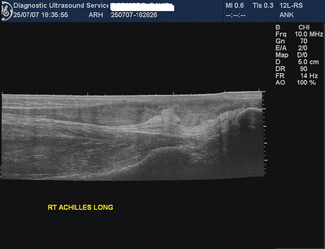

This is an imaging process which combines static B-mode techniques with real-time imaging so that a large subject area can be viewed on a single static image. Extended field of view (FOV) images are obtained by sliding the probe over the area of interest and as the images are acquired they are ‘stitched together’ electronically (Fig. 14.1). The result is a single slice image covering the whole area of interest, for example a full length view of the Achilles tendon (Fig. 14.2). Image feature recognition software is used to combine images.

Fig. 14.2 Extended field image showing the full length of the Achilles tendon